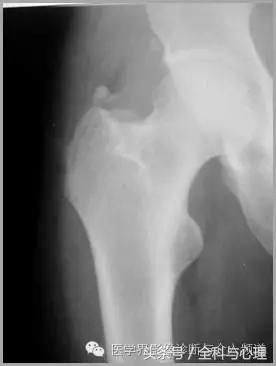

五、滑膜软骨瘤病

1°少见,病灶数量多,大小均匀,相邻关节正常。

2°多见,病灶数量少,大小不一,多伴有退行性骨关节病。

滑膜骨软骨瘤病 1°

滑膜骨软骨瘤病 2°

滑膜骨软骨瘤病